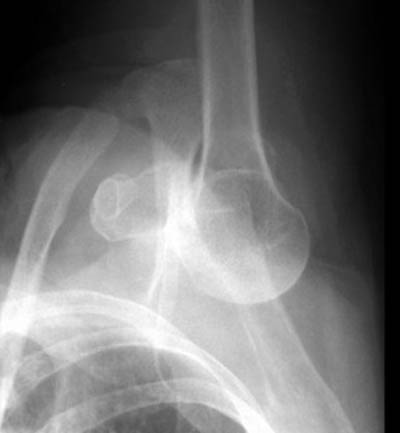

15) Name the abnormality shown in the image below?

16) What anatomical structure can be easily damaged during a dislocation such as the one shown above?